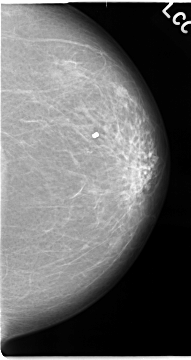

C_0051_1.LEFT_CC

LEFT_CC LINES 4680 PIXELS_PER_LINE 2472 BITS_PER_PIXEL 12 RESOLUTION 50 NON_OVERLAY